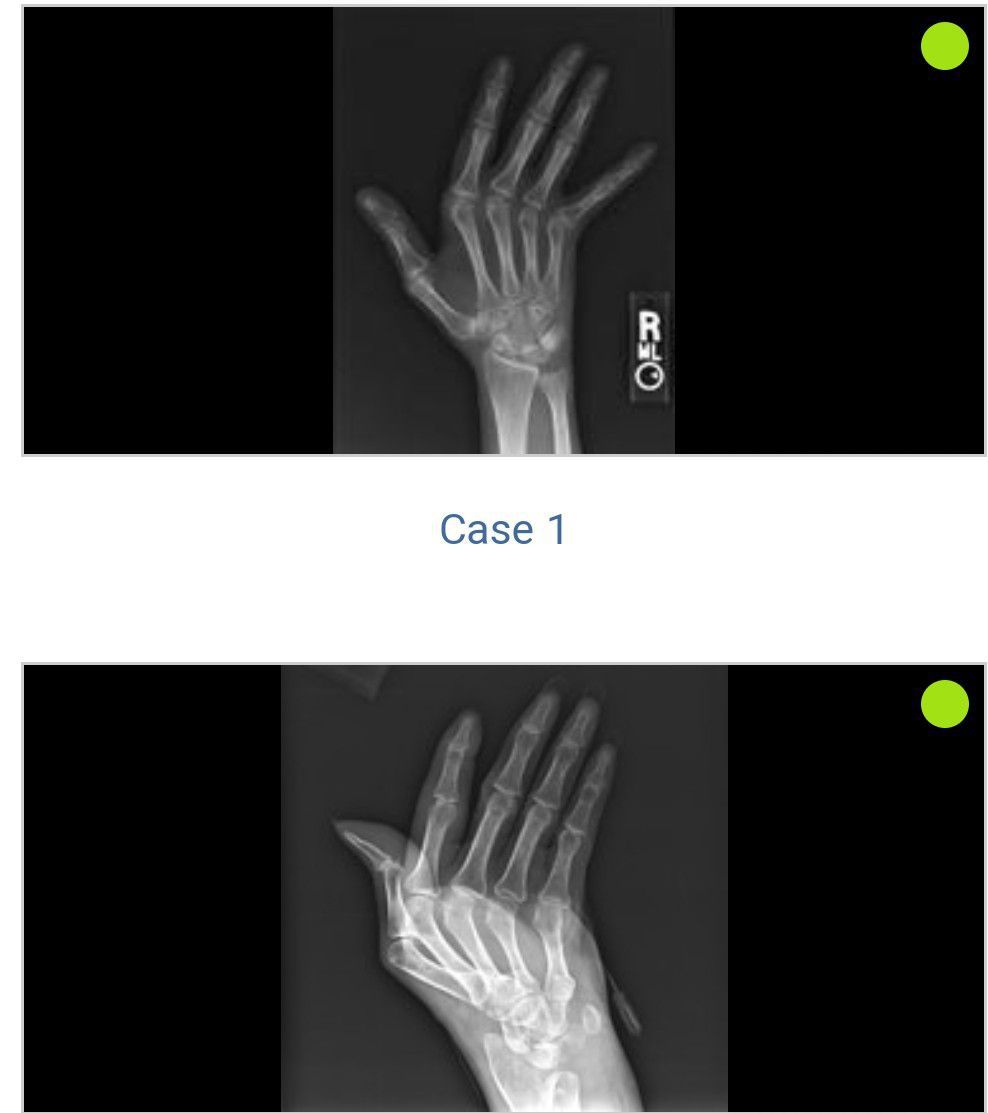

Jaccoud's arthropathy

Non erosive

Sle

Rhematology